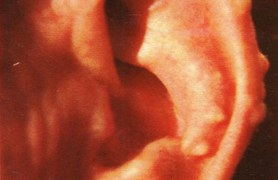

【易发部位】脚拇指关节、拇趾跖关节、跗跖关节、踝关节、手指关节,掌指关节、腕关节、肘关节、膝关节、耳廓。